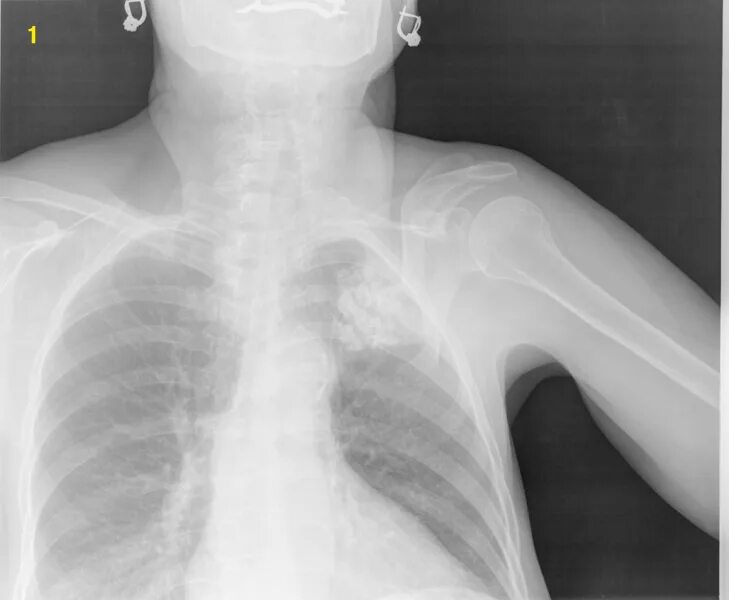

Грудино ключичная артрит